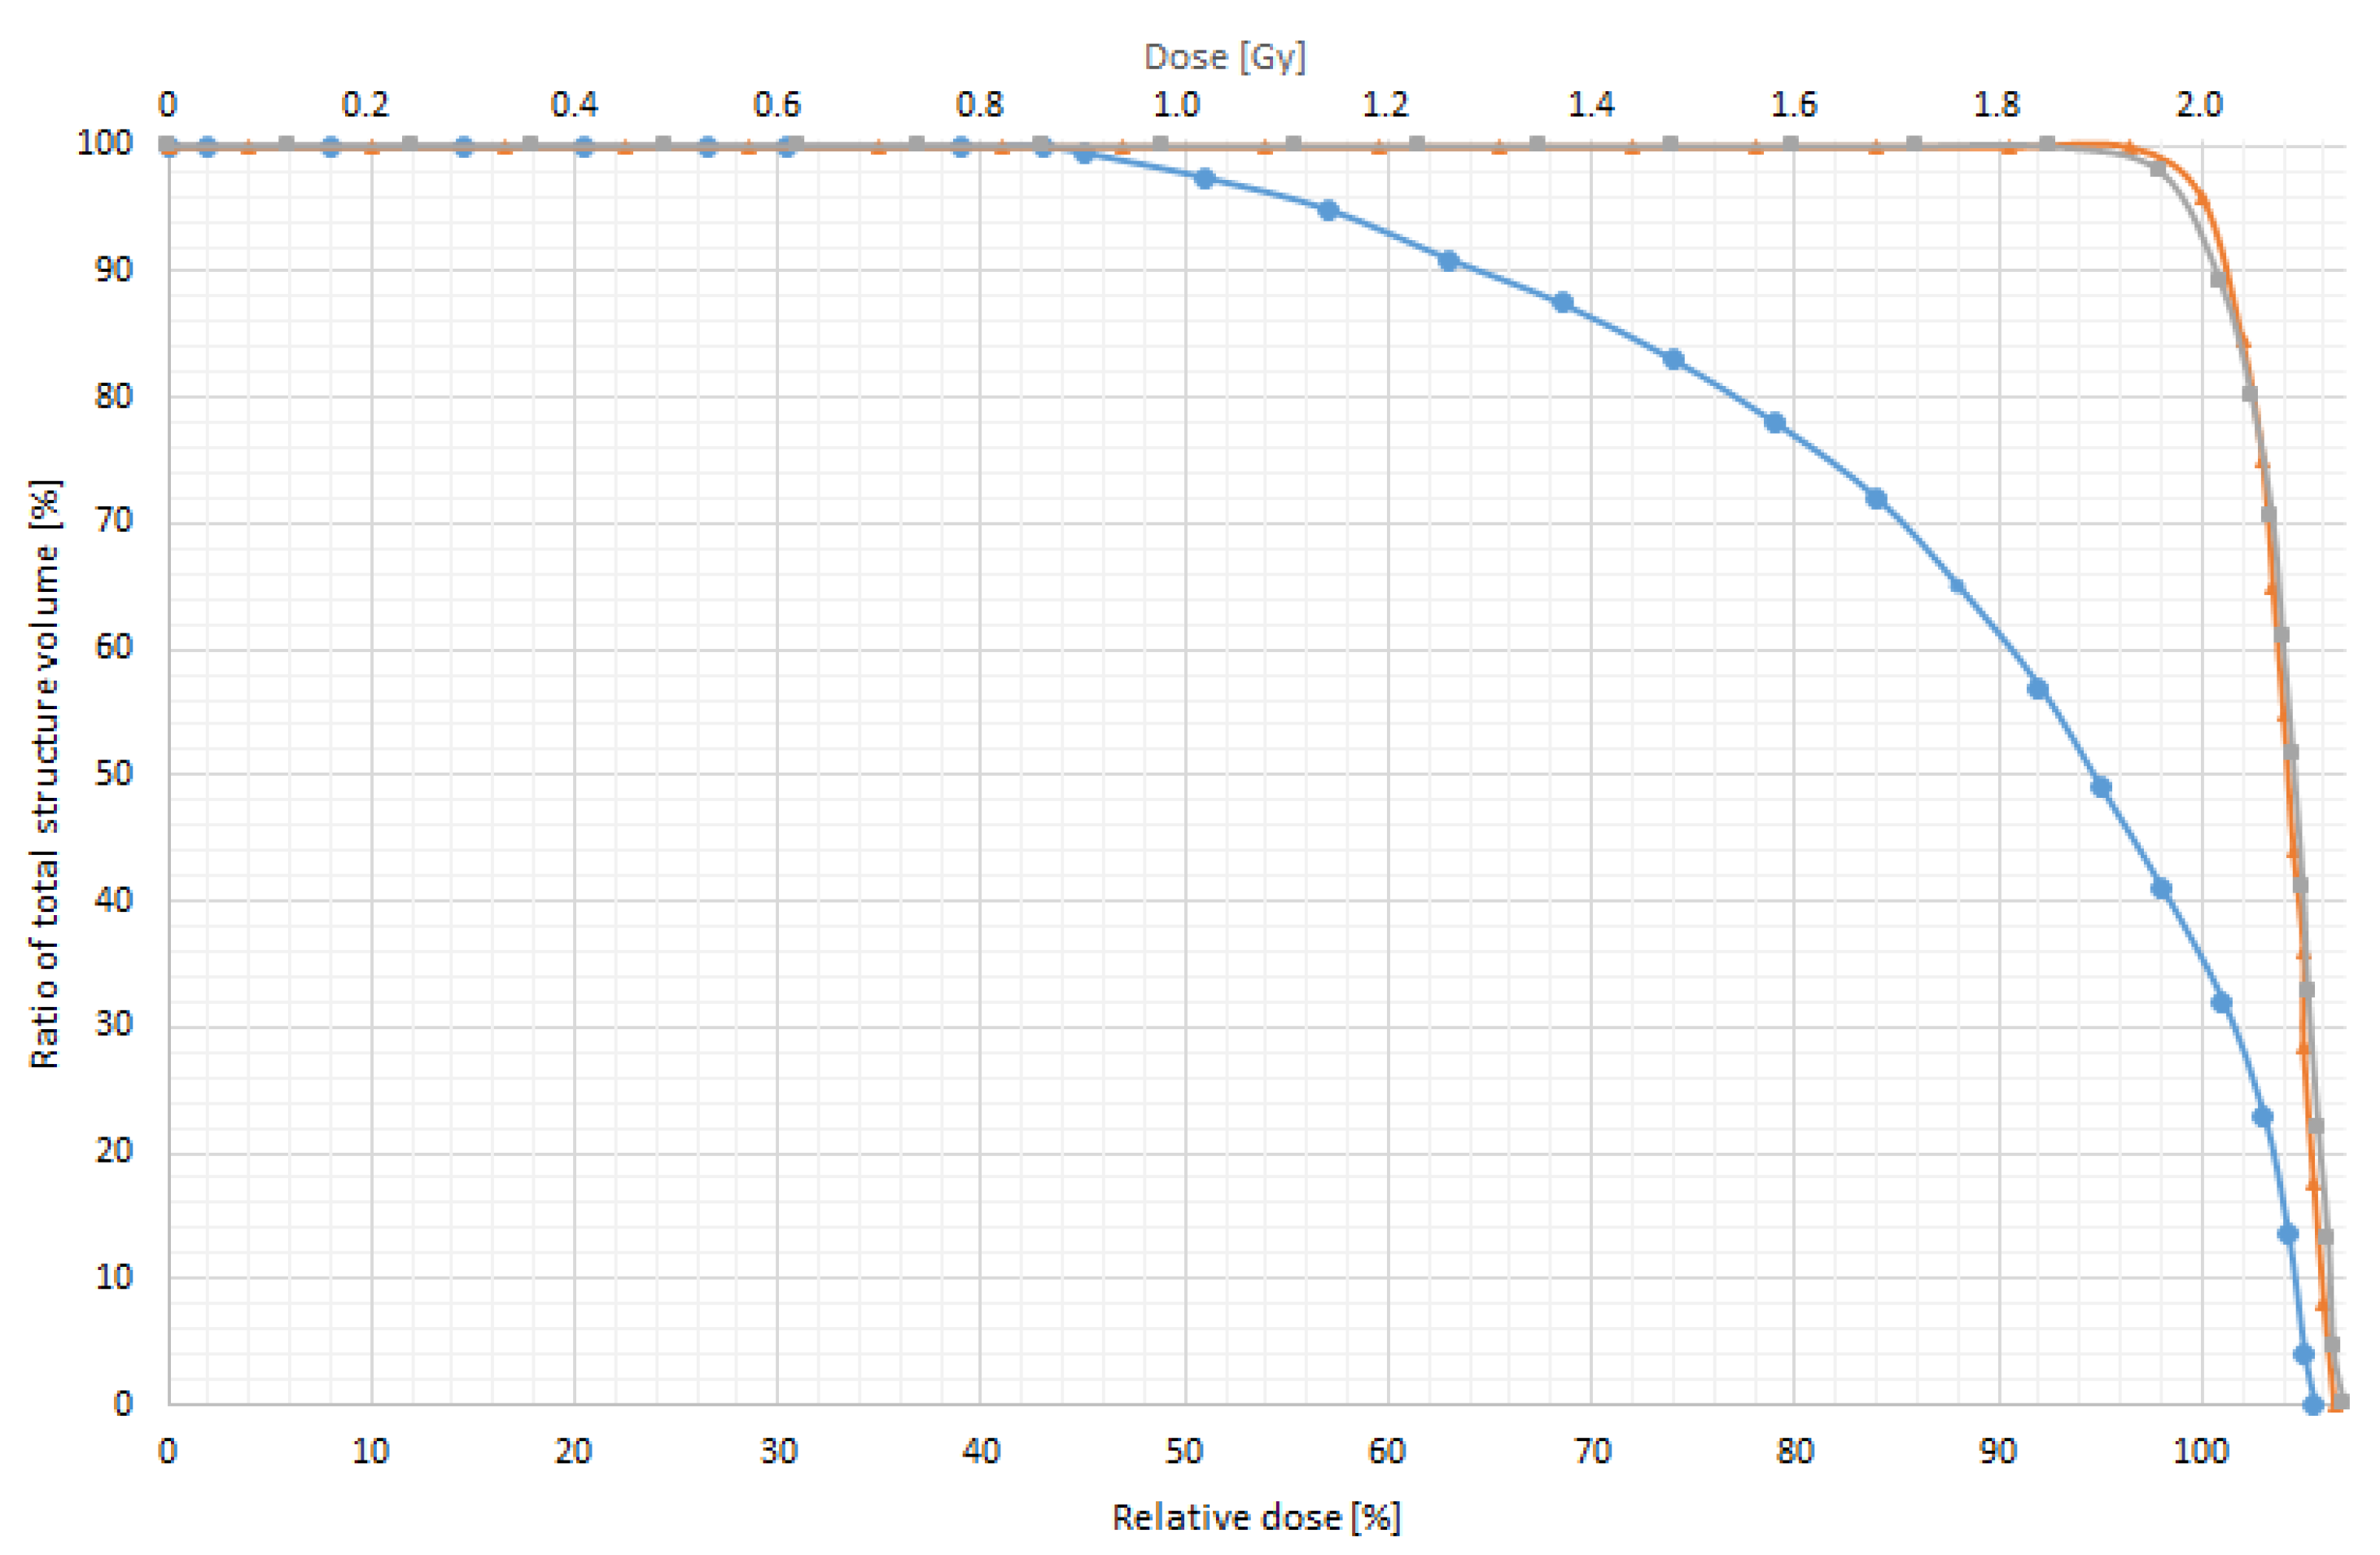

2.4. Dosimetric Evaluation

3.3. In Vitro Dose Verification Using 3D-Printed Devices